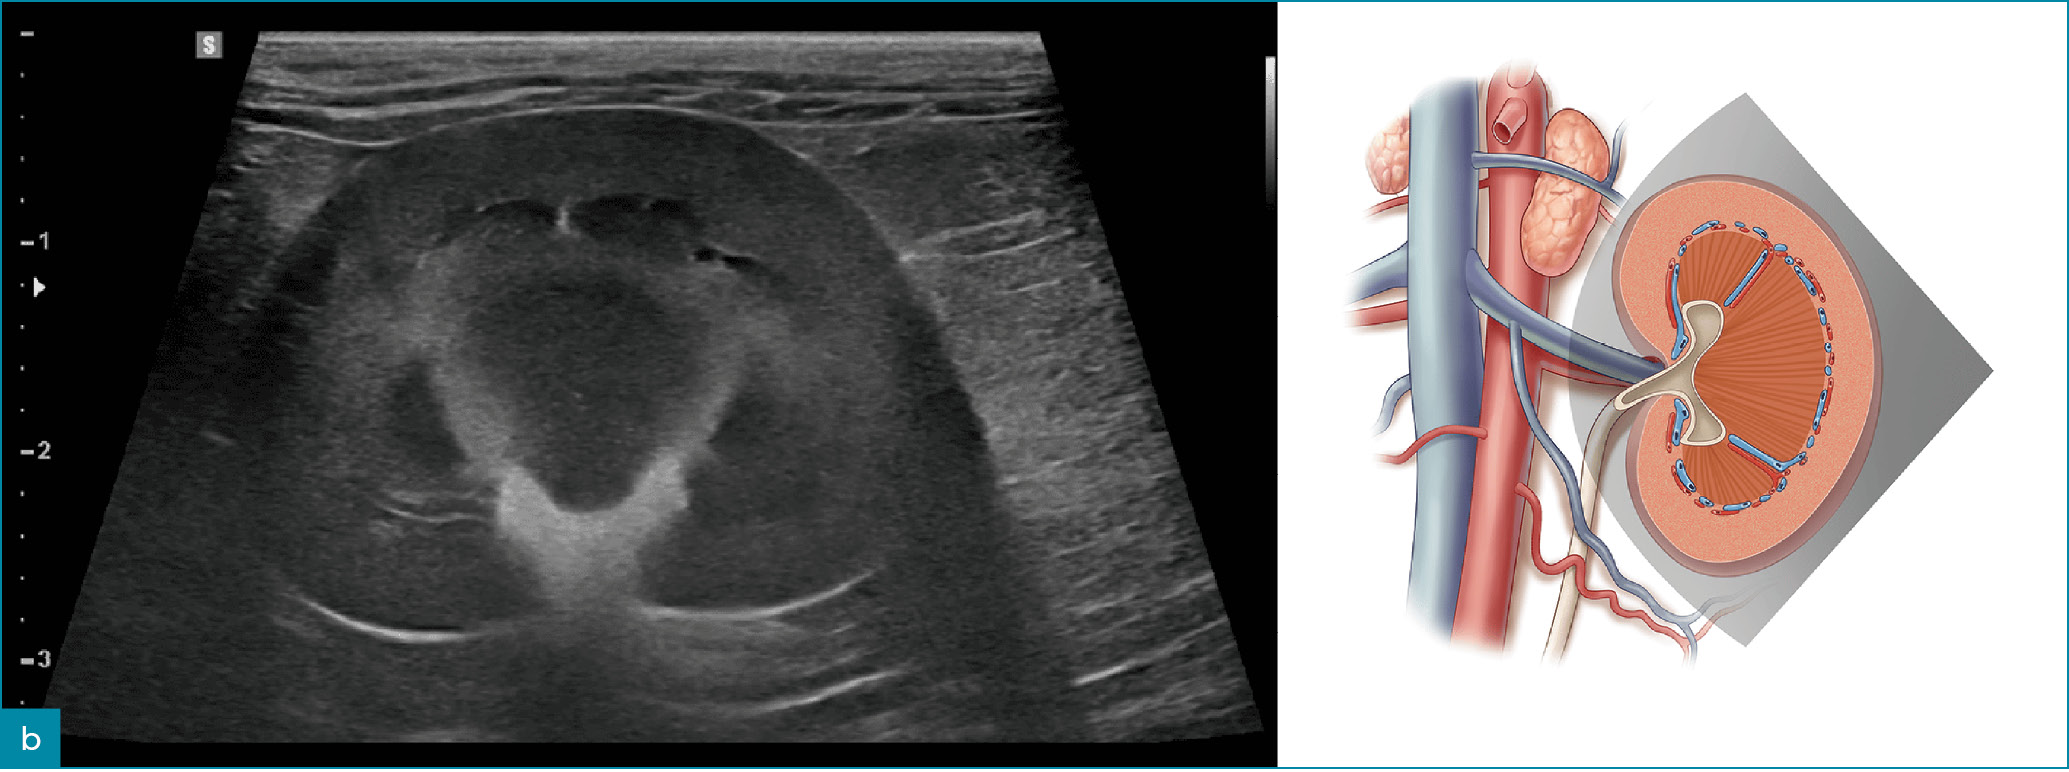

Prawidłowy obraz ultrasonograficzny nerek został szczegółowo omówiony w innych źródłach,7 a poniższy artykuł koncentruje się na przewlekłej chorobie nerek u kotów i psów. Nerki powinny być obrazowane w trzech projekcjach – strzałkowej, dogrzbietowej i poprzecznej (ryc. 1).7 U psów, zwłaszcza małych ras, opisano obecność hiperechogenicznego zewnętrznego pasma rdzeniowego, które obserwuje się z umiarkowaną częstością u pacjentów bez stwierdzonej choroby nerek (ryc. 2).8 U kotów kora nerek może być jednorodnie silnie hiperechogeniczna ze zwiększonym w następstwie zróżnicowaniem korowo-rdzeniowym wtórnym do lipidozy kanalików bliższych (ryc. 3).9 Odkładanie się tłuszczu w kanalikach nerkowych jest konsekwencją otyłości bez jednoczesnego upośledzenia czynności nerek.10 Dodatkowo rutynowo obserwuje się zależny od kąta badania artefaktowy wzrost hiperechogeniczności kory i rdzenia nerek, wtórny do anizotropii, w obszarach, w których kanaliki nerkowe ułożone są prostopadle do płaszczyzny fali ultradźwiękowej. Na przykład podczas obrazowania nerki w projekcji strzałkowej echogeniczność biegunów doczaszkowego i doogonowego będzie ogniskowo i artefaktowo zwiększona (ryc. 4).11 Z doświadczenia autorów wynika, że łagodna nieregularność brzegów nerek, szczególnie u kotów, może być obserwowana w miejscach, gdzie naczynia nerkowe przebiegają wzdłuż torebki nerkowej, i nie powinna być błędnie interpretowana jako zmiana zwyrodnieniowa (ryc. 5). W lokalizowaniu tych naczyń użyteczna jest ultrasonografia dopplerowska kodowana kolorem lub w trybie mocy.

Ryc. 1. Obrazy ultrasonograficzne prawidłowej nerki kota w projekcji: a) strzałkowej, b) dogrzbietowej oraz c) poprzecznej. Towarzyszące ilustracje przedstawiają przebieg płaszczyzn obrazowania.